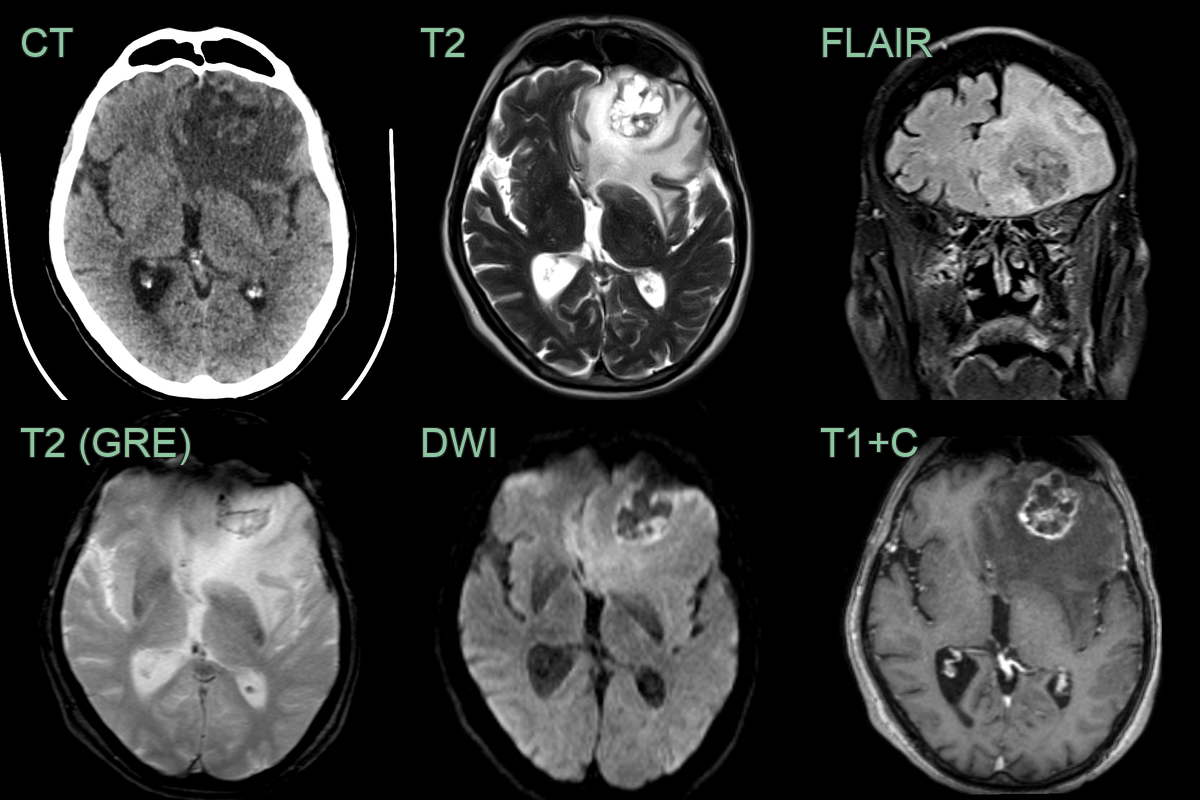

- A 60-year-old patient who was diagnosed with colonic cancer three years prior presented with a right visual field defect and headache.

- A large left occipital lobe lesion showed peripheral enhancement and was surrounded by vasogenic edema.

- The peripheral T2-hypointensity within the lesion has been reported to be related to collagen accumulation.